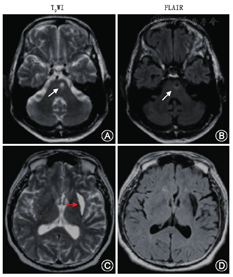

NCCT是临床确诊急性脑出血的首选方法,是脑出血检测的"金标准"。NCCT用于脑血管病的辅助检查需要注意以下几点:(1)对于急诊疑似脑卒中患者首选NCCT,可以明确患者是否有脑出血或蛛网膜下腔出血(subarachnoid hemorrhage,SAH),病灶呈现高密度影,为临床进一步诊治提供重要信息。在疾病的恢复期和慢性期,CT呈低密度影。(2)对疑似SAH患者,首选头颅CT检查。螺旋CT检测的阳性率可达98%~100%。但需要考虑就诊时间,发病24 h后,阳性率开始递减,出血5 d后,阳性率只有50%。SAH患者需要进一步行CTA/DSA以排除动脉瘤。(3)对脑出血患者,NCCT可以提示早期血肿扩大的征象(图1),目前大家比较认同的几个征象为:岛征、黑洞征、混合征、血肿内低密度、血肿边缘不规则和混合密度征,其预测血肿扩大的敏感度、特异度不完全相同[4]。岛征预测血肿扩大的敏感度、特异度分别为44.7%、98.2%[5];黑洞征预测的敏感度、特异度分别为39.3%、95.5%[6,7];混合征预测的敏感度、特异度分别为39.3%、95.5%[8]。(4)对于缺血性脑卒中患者,早期行NCCT的敏感度并不高,一般在发病24 h后,缺血性病灶才开始明显,表现为低密度改变;但早期可见大脑中动脉高密度征,预测大动脉闭塞的敏感度为67%,特异度为82%[9]。陈旧性缺血性脑卒中患者头颅NCCT低密度病灶需要与陈旧性脑出血低病灶相鉴别(图2),后者在T2WI表现为低密度病灶周边低信号环,系含铁血黄素沉积所致。

T1WI图像对不同的软组织结构有良好的对比度,适于观察软组织的解剖结构;T2WI对显示病变的信号变化比较敏感,利于观察病理变化。二者结合有助于病变的定位、定量和定性诊断。缺血性脑卒中的病灶为低信号,一般24 h后出现。脑出血病灶在急性期为高信号,恢复期和后遗期为低信号(软化灶)。

FLAIR是一种特殊序列,使脑脊液呈低信号,可避免脑脊液产生的部分容积效应及流动伪影的干扰,提高了病灶与正常组织的对比度,因此可显示脑脊液边缘易重叠的脑梗死;常规MRI不易区别SAH与脑脊液,而在FLAIR中,血性脑脊液T2值大于脑实质,信号比脑实质高,具有诊断优势,尤其对后颅凹少量出血更有诊断价值。FLAIR被广泛应用于颅脑各类疾病包括缺血性病变、外伤、出血、肿瘤、脑白质病变的诊断中[16]。急性缺血性脑卒中、外伤、脑出血、肿瘤、白质病变在FLAIR可见病灶为高信号,可以结合其他序列进行鉴别诊断。如对急性缺血性脑卒中和脑出血进行鉴别,可行T1WI检查,前者为低信号,后者为高信号;而T2WI与其相反,前者为高信号,后者是低信号;脑白质病变与急性缺血性脑卒中在T2WI和FLAIR上均为高信号,可采用DWI进行鉴别,前者在DWI为等信号或低信号,后者为高信号。